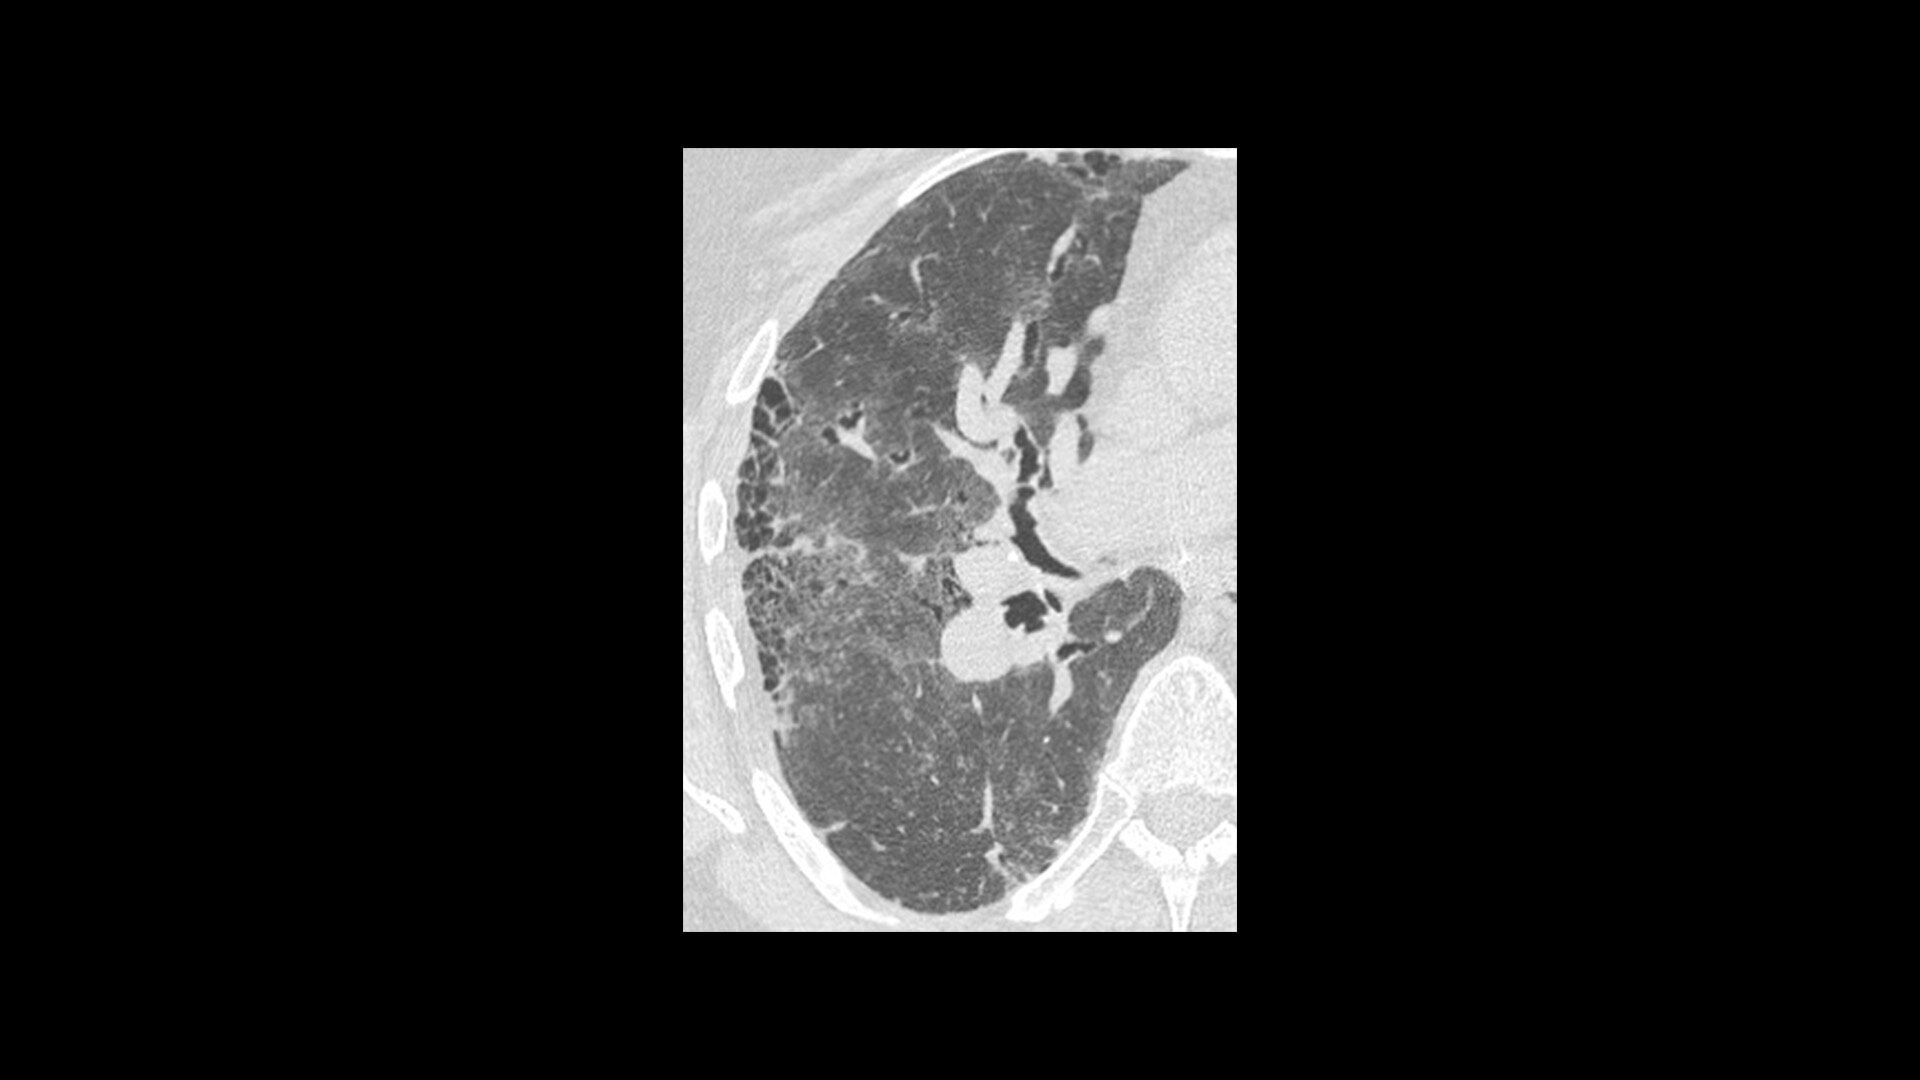

TrueFidelity DL + True Enhance DL

Better together

With the Revolution Ascend Platform, you can combine both of our AI-based imaging reconstruction technologies to create one stunning image. By combining True Enhance DL with TrueFidelity DL, you can achieve images that have less noise, enhanced sharpness and better noise texture than images obtained with ASiR-V.